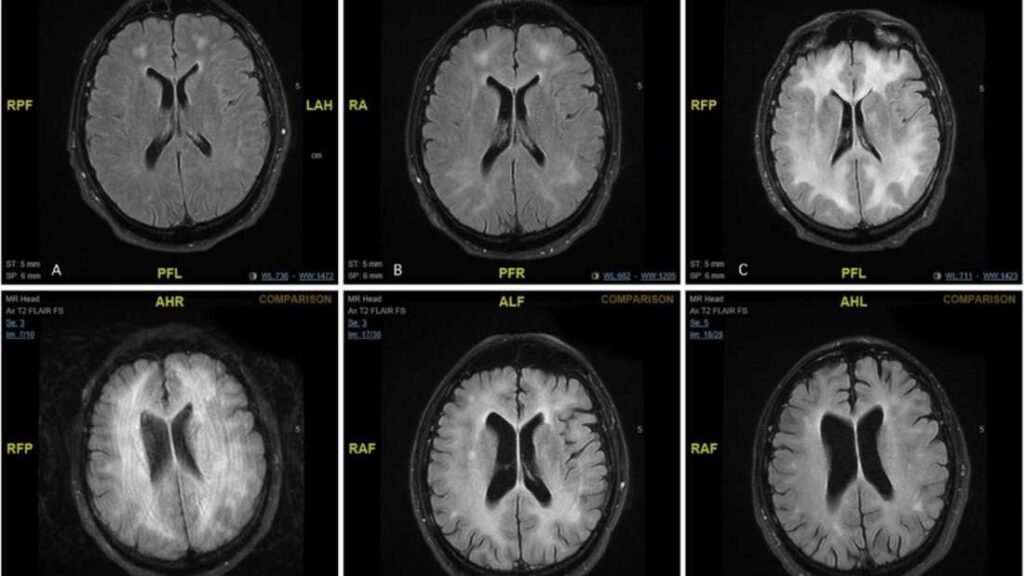

La terrible imagen que vemos en portada forma parte de un caso publicado en BMJ Case Reports. Un hombre de 45 años se presentó en la sala de emergencias de Malta con confusión y comportamiento inusual, y aunque no había consumido recientemente, su adicción a la cocaína lo estaba devorando por dentro. Al parecer, cuando…